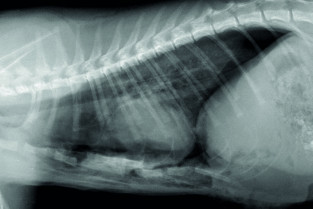

Le GEIM vous propose une séance de travaux pratiques de radiographies sur le thorax. Tous les aspects sont abordés sous la forme de TP de lecture de radiographies numériques sur station de travail Osirix sur Mac (3 vétérinaires maximum/ordinateur).

- adopter une méthodologie pour interpréter les affections de la cage thoracique, de la plèvre, du médiastin et des poumons chez les carnivores domestiques ;

- connaître l’aspect normal et anormal de la cage thoracique, de la plèvre, du médiastin et des poumons chez les carnivores domestiques.